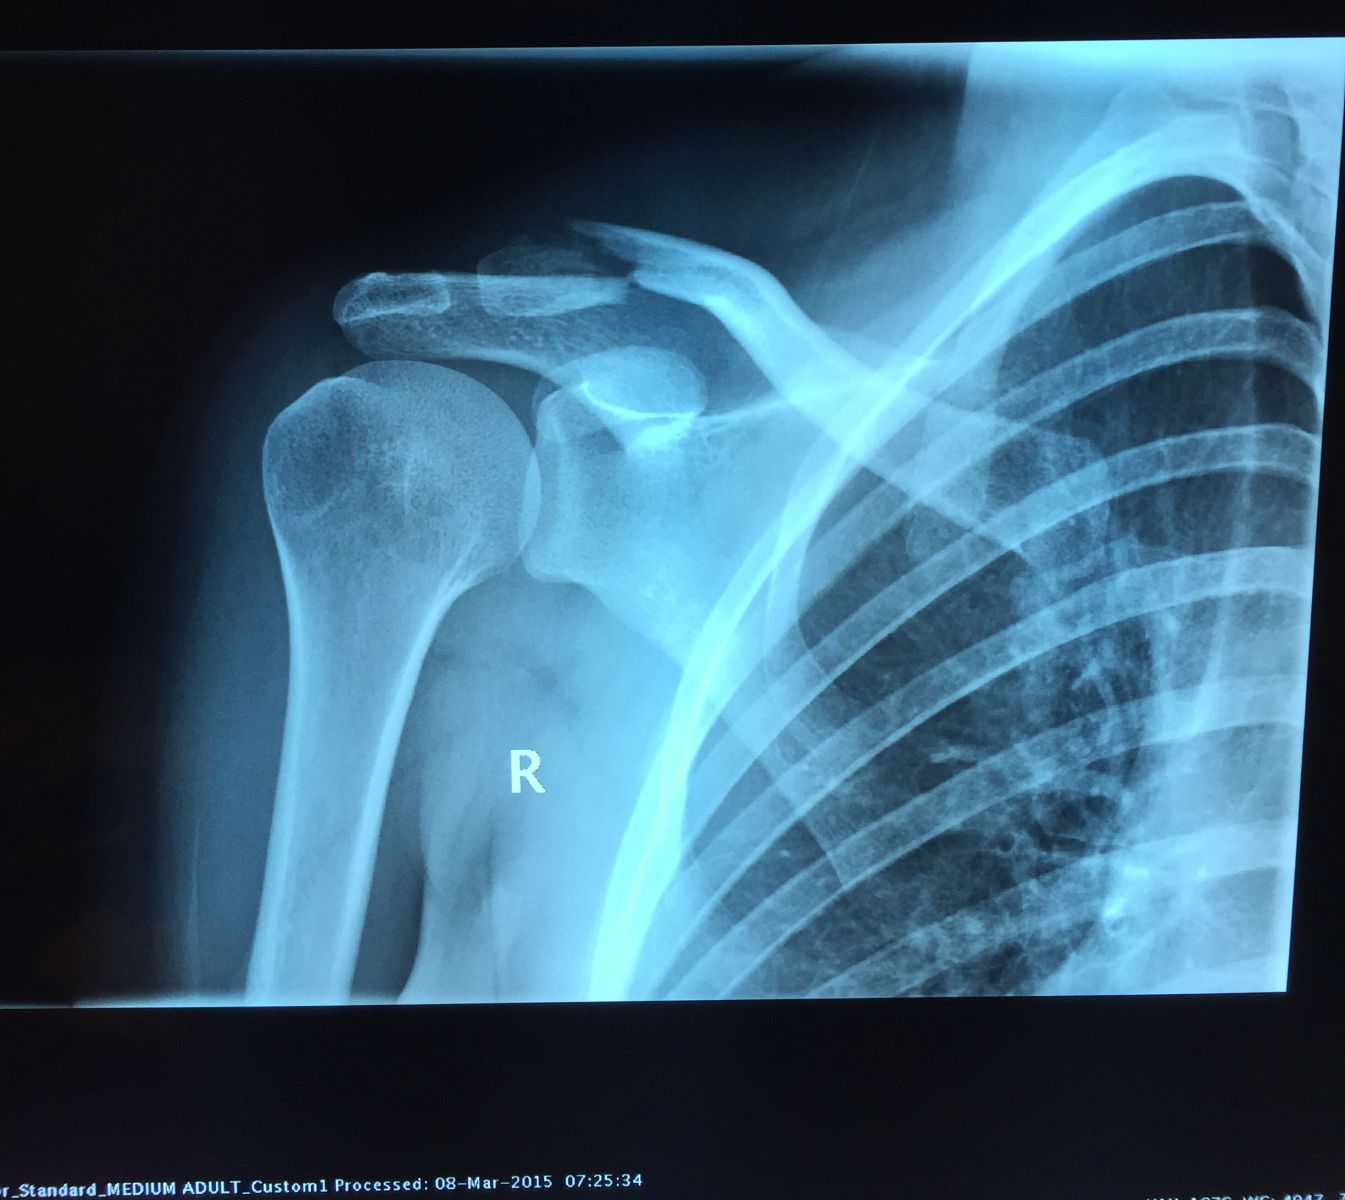

Σε περιπτώσεις μεγάλης συντριβής και παρεκτόπισης, είναι προφανές ότι, υπάρχει κίνηση μεταξύ των κατεαγότων άκρων και δεν μπορεί να εξασφαλισθεί ένα «σταθερό περιβάλλον» που θα επιτρέψει το σχηματισμό πώρου, πέραν του άλγους και της δυσχέρειας κινήσεων. Στις περιπτώσεις αυτές, η θεραπεία του κατάγματος είναι χειρουργική. Τέτοιες περιπτώσεις, περιλαμβάνουν κυρίως τα παρεκτοπισμένα κατάγματα του μέσου και έξω τριτημορίου της κλείδας.

Τα κατάγματα του έξω τριτημορίου της κλείδας αποτελούν ιδιαίτερη κατηγορία διότι,συχνά συνοδεύονται από συνδεσμικές βλάβες (βλέπε εξάρθρημα ακρωμιοκλειδικής). Στις περιπτώσεις αυτές, πέραν της οστεοσύνθεσης, πραγματοποιείται και ανακατασκευή των τραυματισμένων συνδέσμων. Στην περίπττωση αυτή τροποποιείται ανάλογα και το πρόγραμμα μετεγχειρητικής αποκατάστασης.

Προεγχειρητικά

Προεγχειρητικά